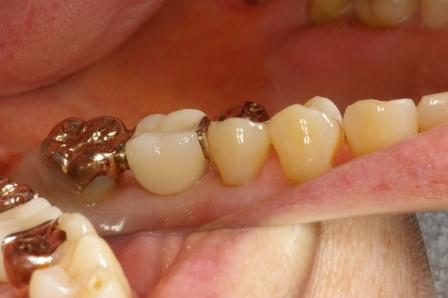

続いて奥歯のブリッジの症例です。

奥歯の2本を土台にしてブリッジを入れました。歯のないところにはブリッジを入れる治療が現在までの主流でした。

ただし、歯のないところにインプラント(人工の歯根)を植えると、土台の歯は削らないですみます。